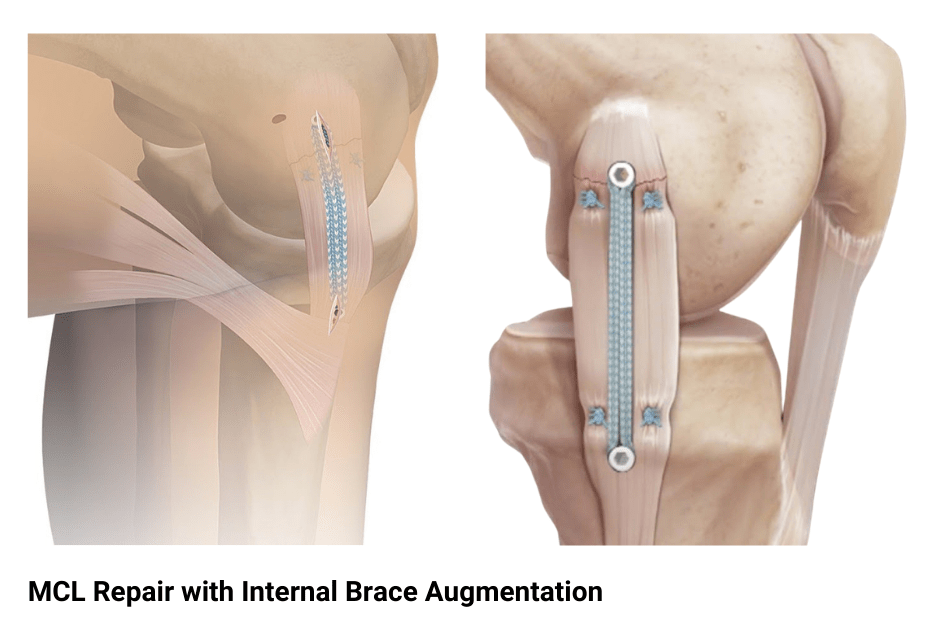

The repair work can be done in 1 of 2 ways: Tendon from another area may be. An mcl graft can be.

There are two primary types of mcl surgery: While most mcl injuries can resolve without surgery, there are instances where surgery is the best treatment option. You’ll need to raise your sore knee when you put ice on it, keep weight off the joint, and protect and compress the injury with a knee brace or elastic bandage.

Treatment options for an mcl sprain. The surgery will either repair or reconstruct the mcl. A total rupture of the mcl usually doesn’t require surgery.